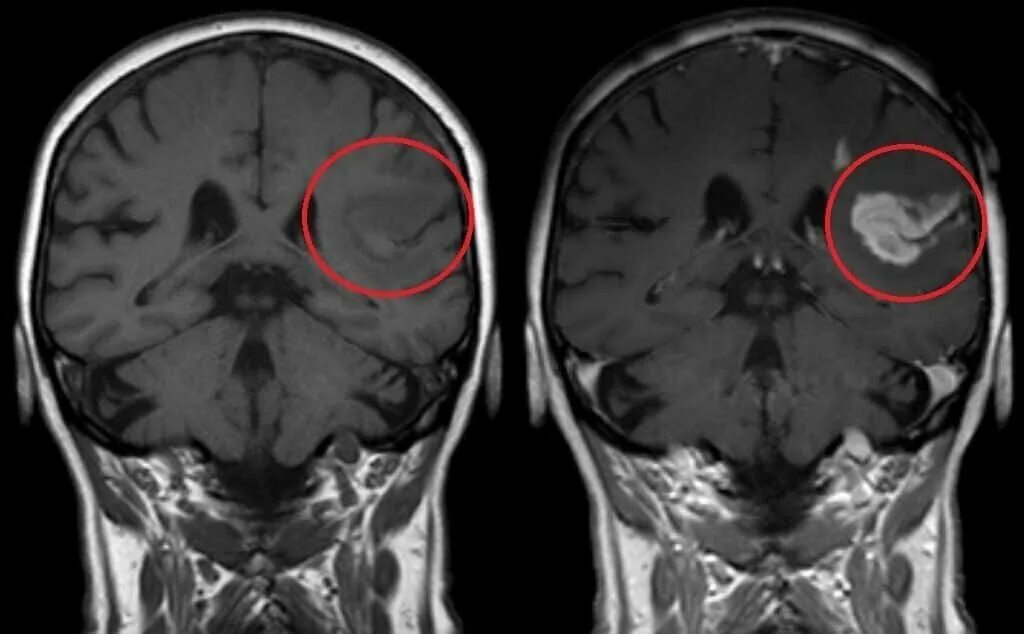

Чем отличается мрт от мрт с контрастом